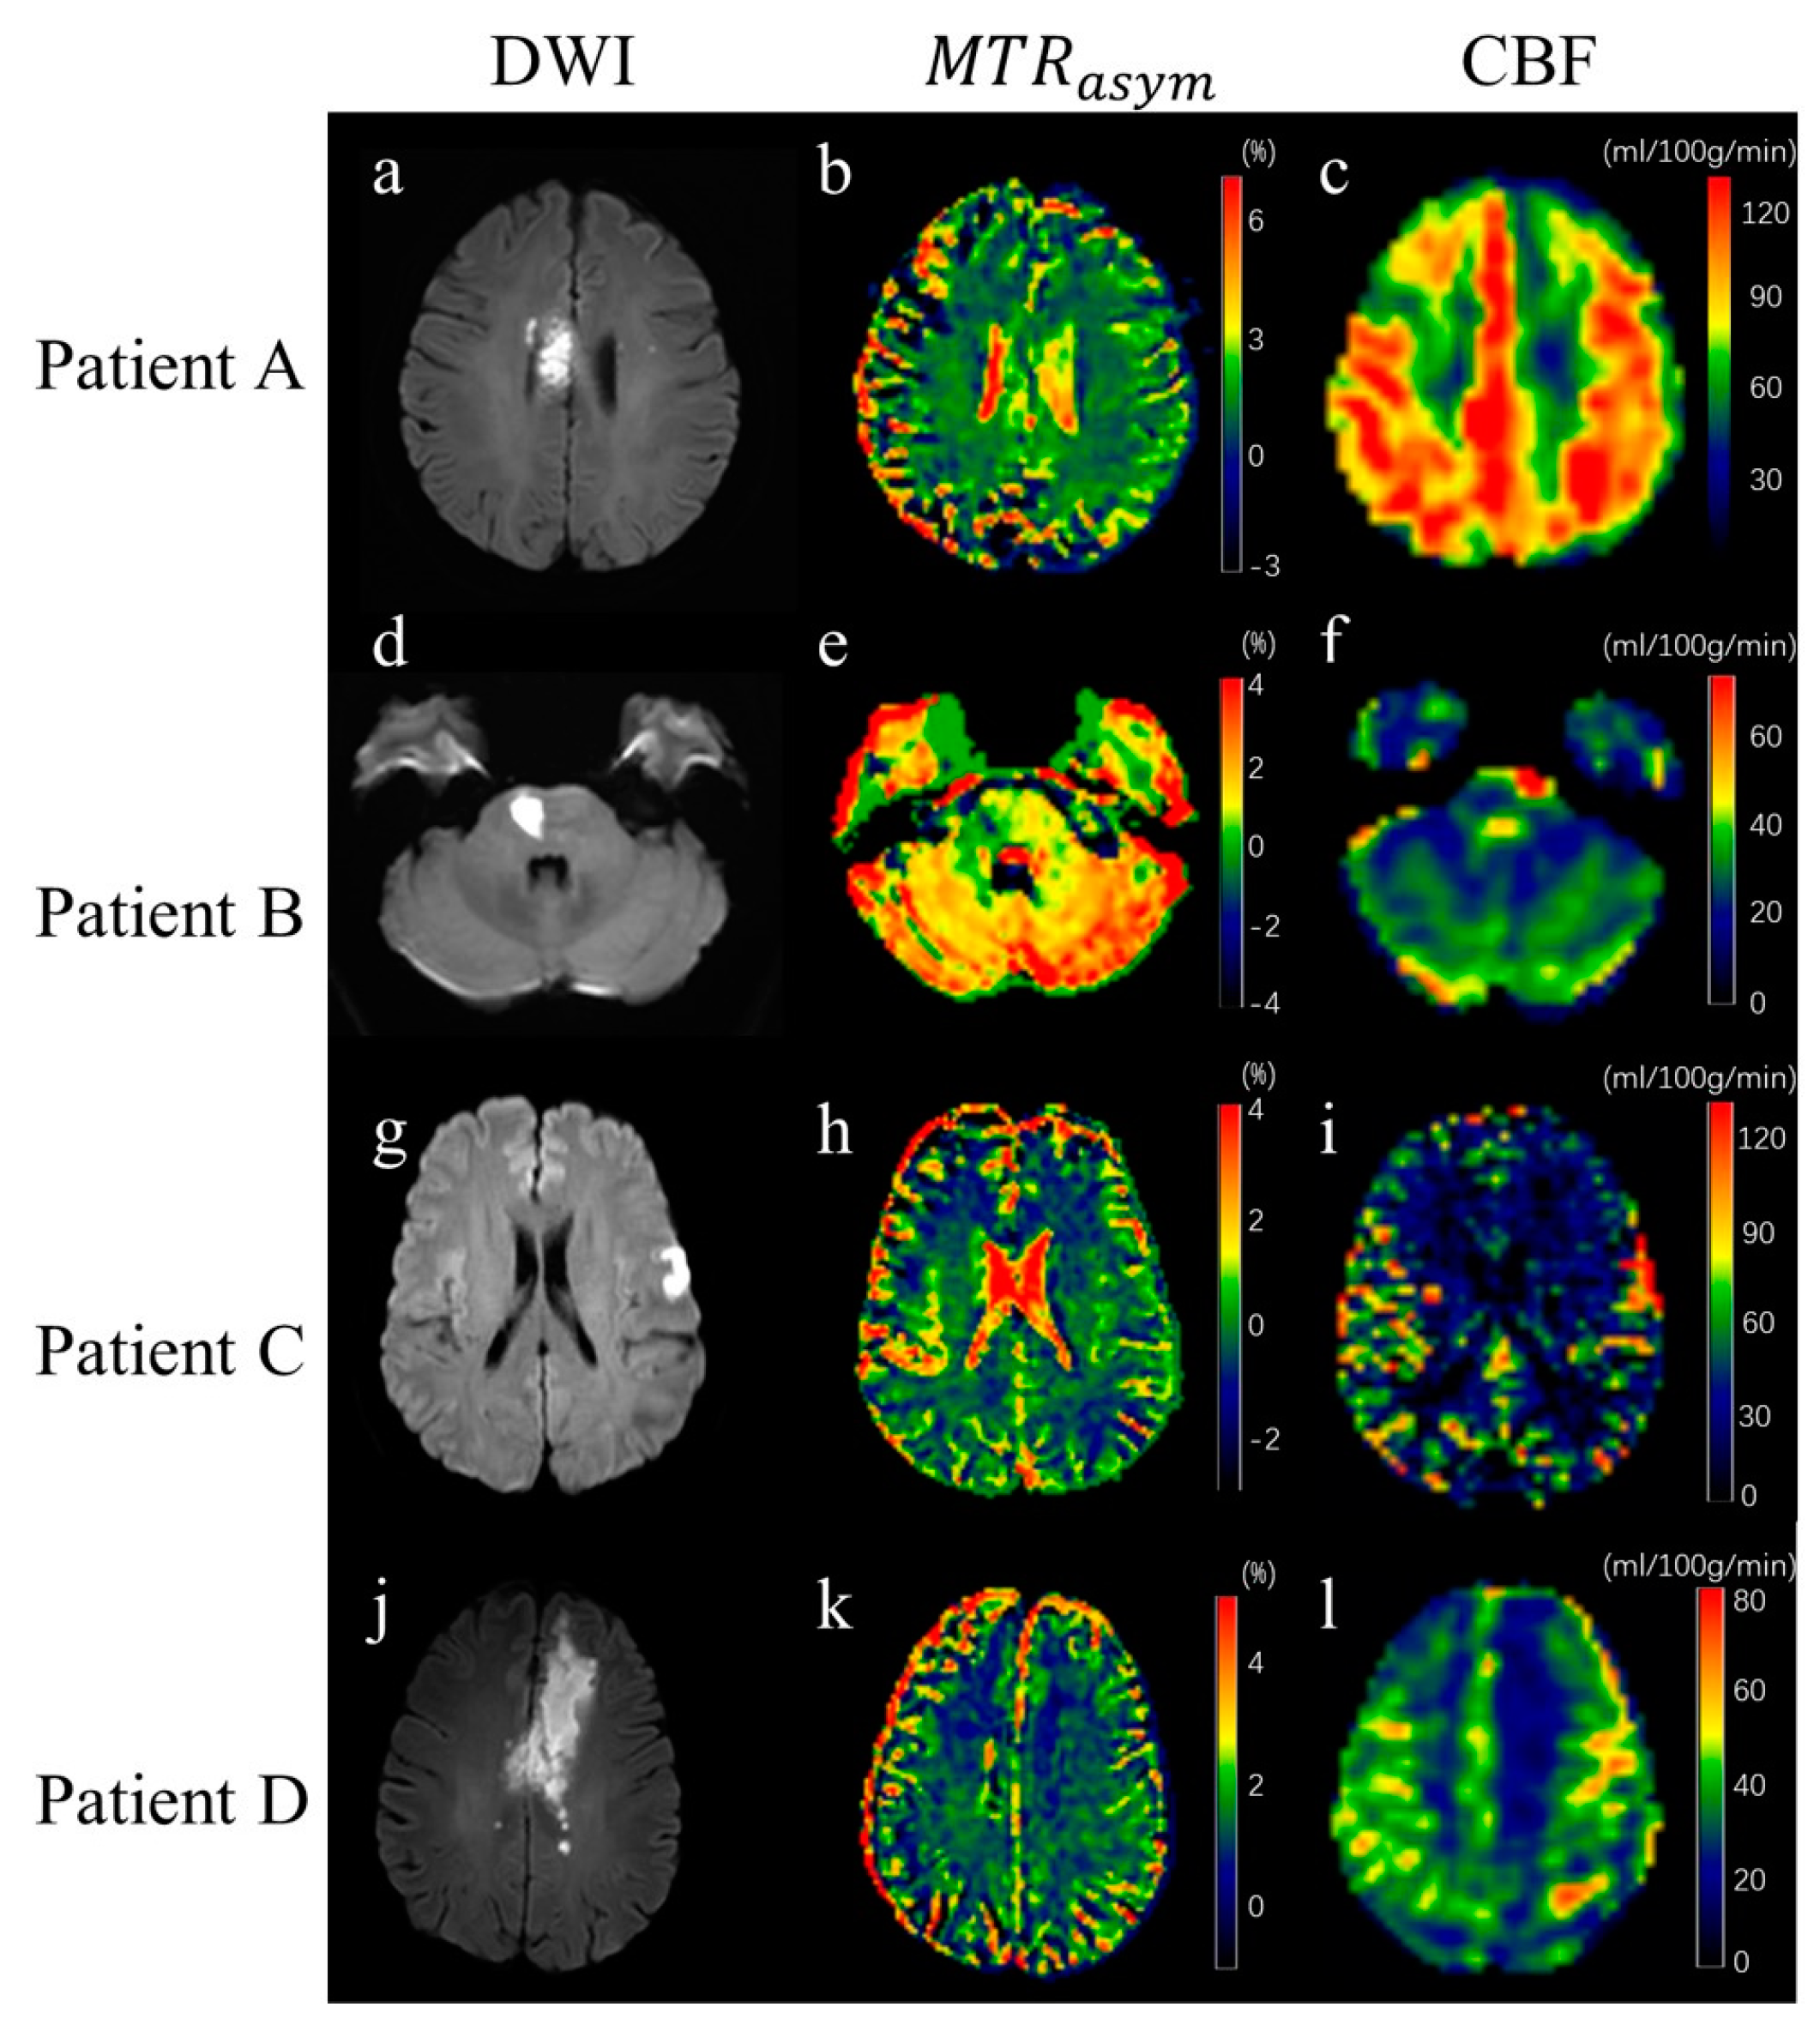

3.2. Image of Stroke Patients